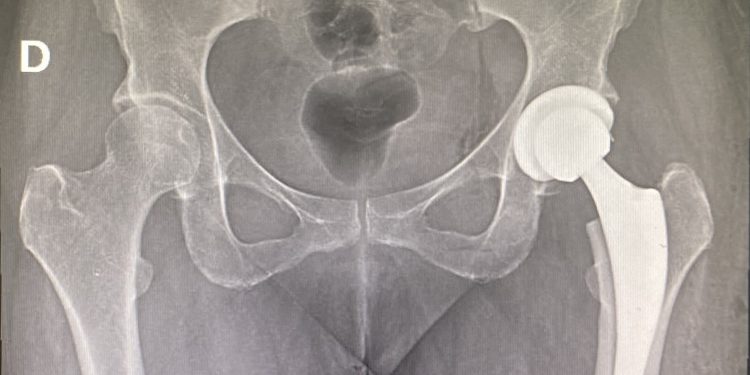

El profesional resalta que las prótesis empleadas en la clínica son de titanio de primer nivel, siendo su procedencia americana o alemana. “Existen dos tipos grandes de prótesis. Aquellas que usan cemento para fijar la prótesis al hueso. Y otras que no usan cemento y que van fijadas directamente al hueso. Nosotros, en el casi 100% de los casos, usamos la prótesis no cementada que va fijada directamente al hueso, independiente de la edad del paciente”. Destaca que el titanio es un metal que se adapta muy bien con el hueso y permite que el hueso crezca en su interior, siendo muy baja la tasa de rechazos a las prótesis.

Explica que en el preoperatorio, el paciente lo primero que debe hacer es consultar con un cirujano para determinar si corresponde o no la indicación de la prótesis de cadera. Posteriormente, hay que analizar la radiografía de la pelvis para definir cuál de los dos modelos de prótesis se adapta mejor a la cadera del paciente.